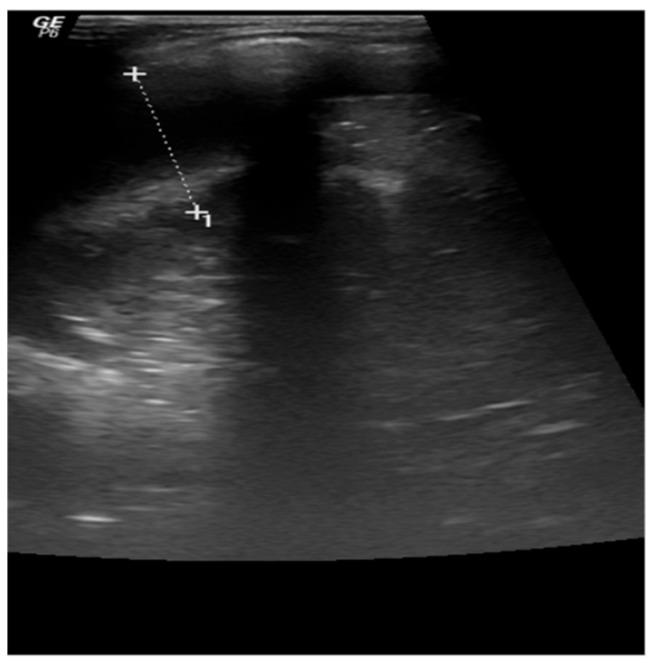

Hemophagocytic lymphohistiocytosis (HLH) is a rare, and potentially fatal, syndrome, characterized by immune system dysregulation, with excessive activation of the macrophages and cytotoxic T cells. It can be classified into primary (genetic) and secondary (acquired) forms. HLH presents with fever, hepatosplenomegaly, cytopenia, and hyperferritinemia, with involvement of various organs. The initial symptoms of HLH are non-specific, but as, if untreated, it can progress rapidly to multiorgan failure, timely diagnosis is essential. We present here two cases of HLH in infants that illustrate the importance of early diagnosis and appropriate treatment, along with a short review of HLH.

噬血细胞性淋巴组织细胞增生症(HLH)是一种罕见且可能致命的综合征,其特征为免疫系统失调,巨噬细胞和细胞毒性T细胞过度活化。它可分为原发性(遗传性)和继发性(获得性)形式。HLH表现为发热、肝脾肿大、血细胞减少和高铁蛋白血症,并累及多个器官。HLH的初始症状不具特异性,但如果不治疗,它可迅速进展为多器官功能衰竭,因此及时诊断至关重要。我们在此介绍两例婴儿HLH病例,阐述早期诊断和恰当治疗的重要性,并对HLH进行简要综述。